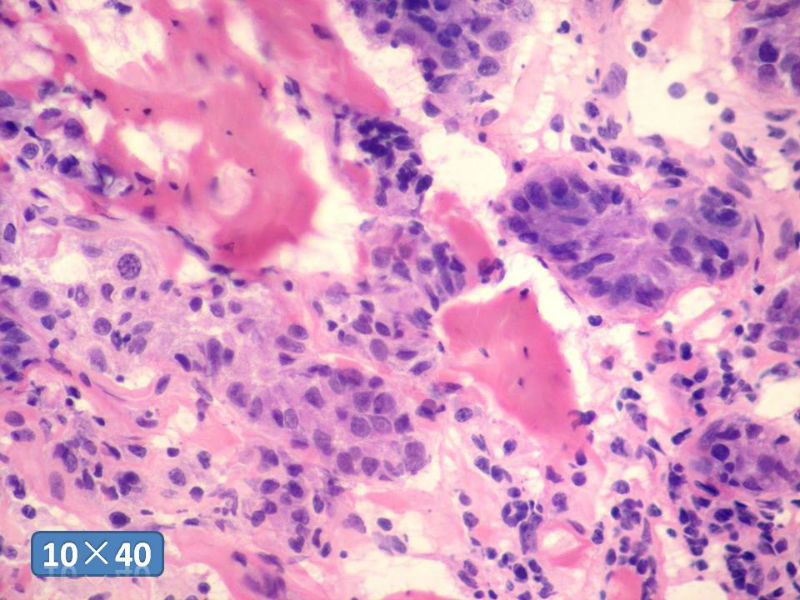

女性,50岁,乳腺肿物,冰冻切片(图1-25)

HE